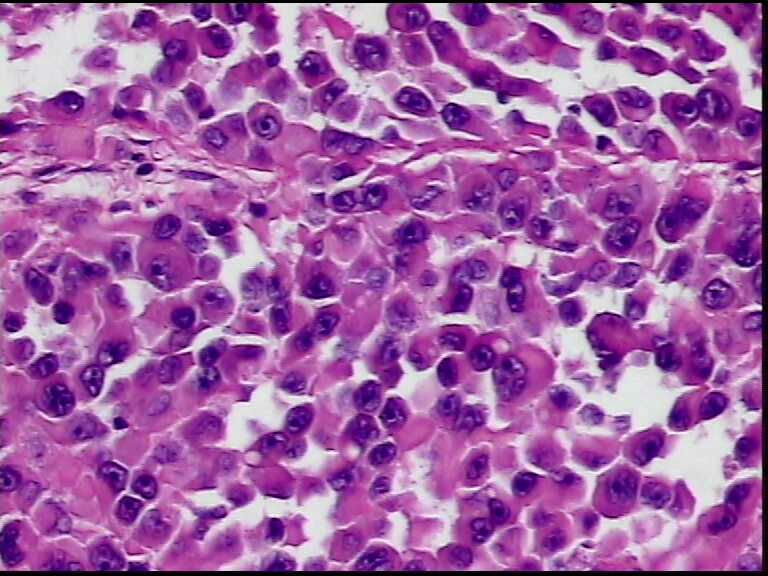

患者男性,34岁,临床没给提供,该患者梅毒阳性

• 请各位老师会诊一下 颌下淋巴结图2

图2

颌下淋巴结肿大,送检肿物直径2.5cm,切面灰粉色,质地嫩,先做了个LCA瘤细胞阴性

淋巴结内见大量宽而嗜酸性胞浆的肿瘤细胞,瘤细胞核大,偏心分布,核仁明显,成上皮样表现,部分似有腺泡样排列,符合淋巴结转移性恶性肿瘤,首先除外转移癌,恶性黑色素瘤,继而除外浆细胞瘤(岁数不太符合),横纹肌肿瘤等。

淋巴结内见大量宽而嗜酸性胞浆的肿瘤细胞,瘤细胞核大,偏心分布,核仁明显,成上皮样表现,部分似有腺泡样排列,符合淋巴结转移性恶性肿瘤,首先除外转移癌,恶性黑色素瘤,继而除外浆细胞瘤(岁数不太符合),横纹肌肿瘤等。同意楼上的观点。